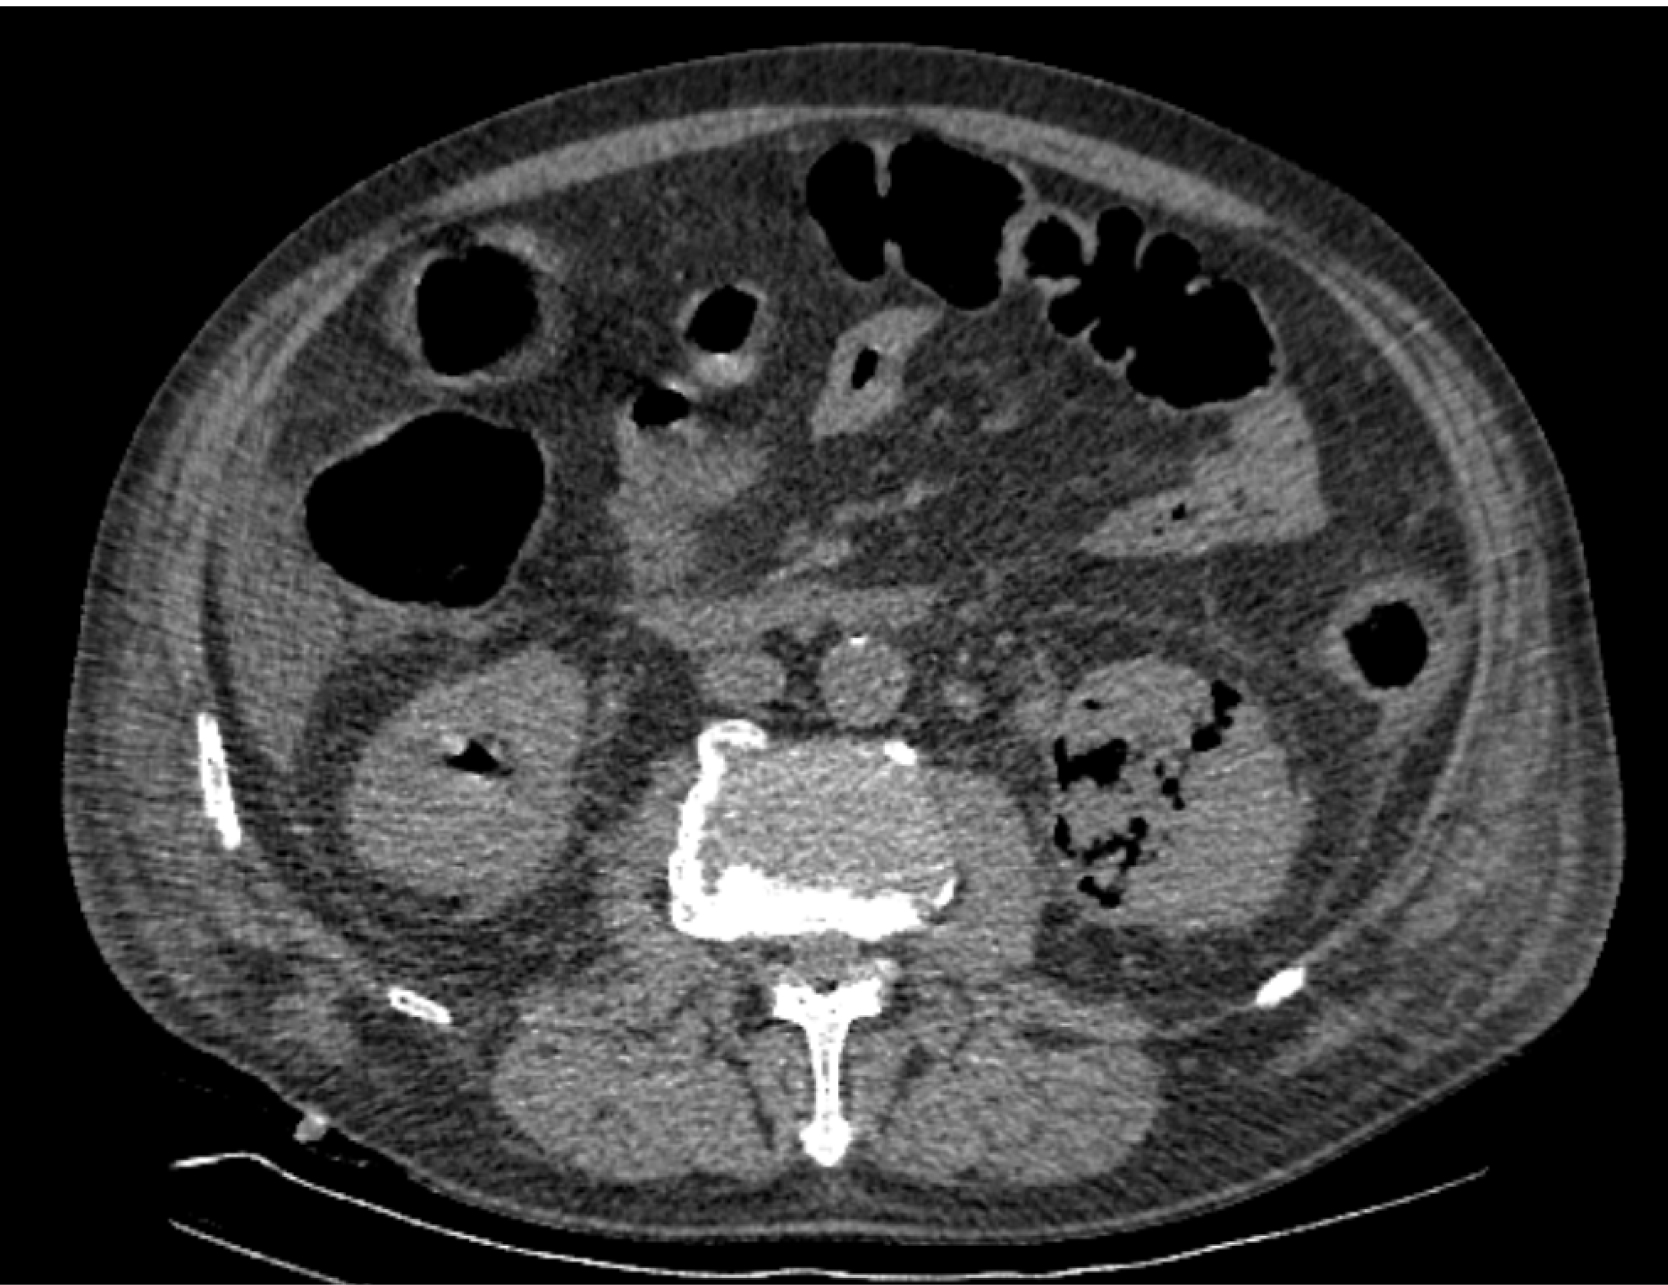

На следующий день состояние пациента оставалось тяжелым, с отрицательной динамикой, креатинин сыворотки возрос до 735,2 ммоль/л, Появились жалобы на слабость, тошноту. При осмотре: живот мягкий, вздут по всем отделам, при пальпации болезненный. Область почек не изменена, при пальпации безболезненна, патологических изменений в области почек не выявлено. Симптом поколачивания отрицательный билатерально. При УЗИ были обнаружены плевральный выпот по 300–400 мл с каждой стороны, гепатомегалия, увеличение размеров селезенки, асцит. Кроме того, в обеих почках были визуализированы тени, характерные для конкрементов. По данным компьютерной томографии (КТ) конкрементов не обнаружено, но в лоханке, на всем протяжении левого мочеточника и, частично, в правом мочеточнике, а также в мочевом пузыре визуализировался газ (рис. 1–6).

Рис. 5. Компьютерная томография органов брюшной полости, забрюшинного пространства, органов малого таза. Газ в левой почке

Рис. 6. Компьютерная томография органов брюшной полости, забрюшинного пространства, органов малого таза. Газ в верхнем полюсе левой почки